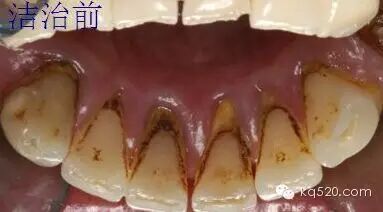

牙周病发病率高,已经超过龋齿成为失牙的首要原因。去除牙体上的菌斑和牙石是牙周病的主要治疗方法。根据顾客牙结石的数量和类型决定洗牙的次数,轻中度牙周病可以一次性洗完。现以较重牙周病为例谈谈我的经验:

较重牙周病一般分两次治疗,第一次先用锐匙去除大块牙结石,再用超声波去除绝大部分龈上牙结石使用洁牙机时要轻柔注意观察顾客的面部表情,如顾客有不良感觉下手应轻点,如还有感觉可换手用器械操作。牙石基本去除后用锄形器械刮至比较光滑为至。因较重牙周病易出血第一次把龈上大部分结石去除即可,不用抛光,牙周袋内上碘甘油。给顾客开甲硝唑和螺旋霉素7天量。瞩1周内勿食过冷过热的食物。

有较重牙周病的顾客一般游离龈和龈乳头呈鲜红色或暗红色,牙龈组织肿胀,龈缘变厚,服药7d后病人牙龈组织肿胀充血现象明显减退,刷牙出血等现象消失,这时龈下洁治视野清楚,先用超声波彻底去除龈上及龈下可见牙石,再用手用器械去除龈下牙石。手用器械去除龈下牙石手感好,顾客无不良反应的优点。